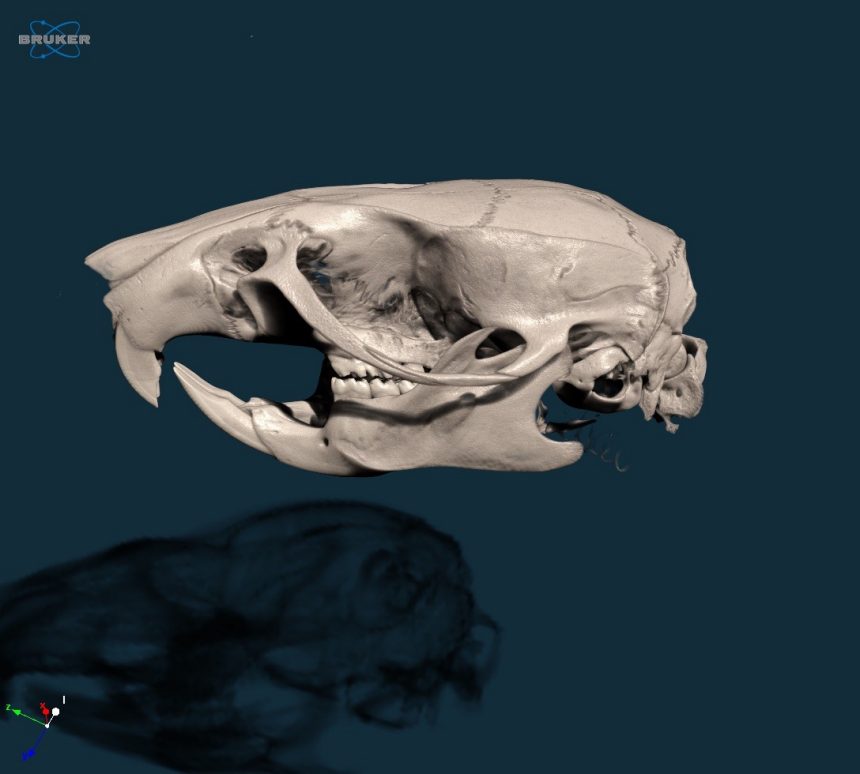

2. 3D model of a rat skull, scanned at 20um voxel size in vivo